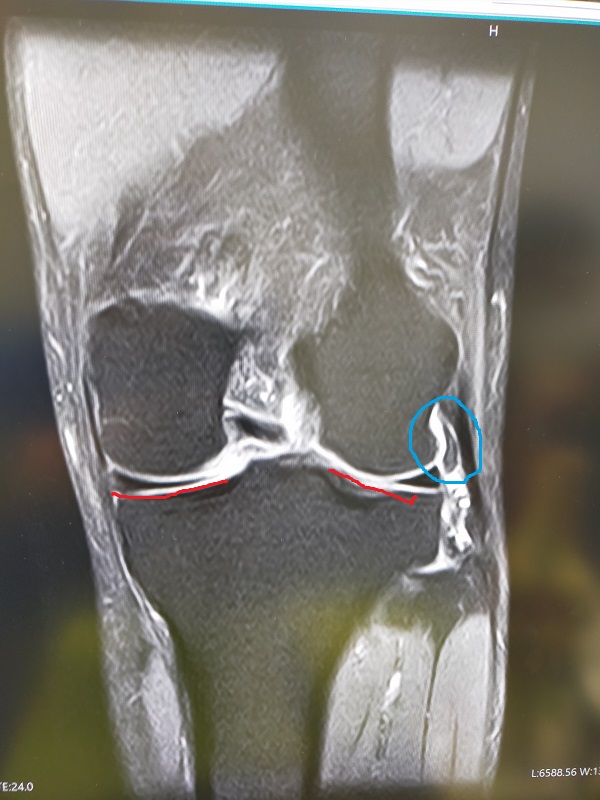

靭帯    ..キミ     返信

.jpg / 163.5KB このMRI画像の赤い部分が

前十字靭帯と後ろ十字靭帯と思う

これと量左右に靭帯があるようで

靭帯損傷などは見られない